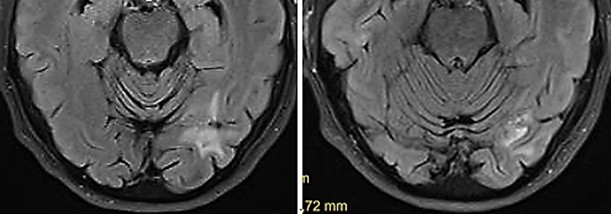

Fig. 6

Fig. 6: Occipital metastasis six months (left) and twelve months (right) after transcranial TMI treatment with glial scar. Notably the brain tissue is not impaired by the transcranial TMI treatment

A now 76 years-old female patient suffered since 2013 from a metastatic malignant superficial spreading skin melanoma (pT3aN3cM1c) in the right gluteal area. After resection of the primary tumor and repetitive resections of cutaneous and subcutaneous metastases situated between the primary tumor and the regional lymph nodes (in-transit filiae), and metastases in the regional lymph nodes, and after immunotherapy cycles with Nivolumab, in 2020, an occipital brain metastasis occurred. Nivolumab immunotherapy was resumed, applying 25 cycles. Five extracorporeal TMI treatments (4, 000 impulses each within 20 minutes) were applied to a cutaneous metastasis. As well the treated tumor as the not treated metastases regressed significantly. In June 2024, transcranial TMI treatment of a new occipital metastasis was applied. The treated brain-metastasis regressed. Controls six, twelve and twenty months, the latter in February 2026, after transcranial TMI treatment did not show any new metastases and no vital tumor tissue in the glial scar remnants of the regressed metastasis (Fig. 6).